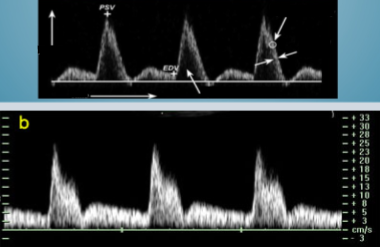

Which form of doppler imaging is seen here?

Continuous wave

With continuous wave doppler, what doppler finding is expected/normal even with laminar flow?

Spectral broadening

Pulsed doppler will produce what kind of spectral waveform when a limited number of frequencies or velocities are evident in laminar flow?

Narrow, well-defined

Which of the 2 will consider spectral broadening a normal finding?

Continuous wave doppler

Pulse wave doppler

Which of these 2 waveform images represents a waveform seen on a continuous wave doppler?

Bottom